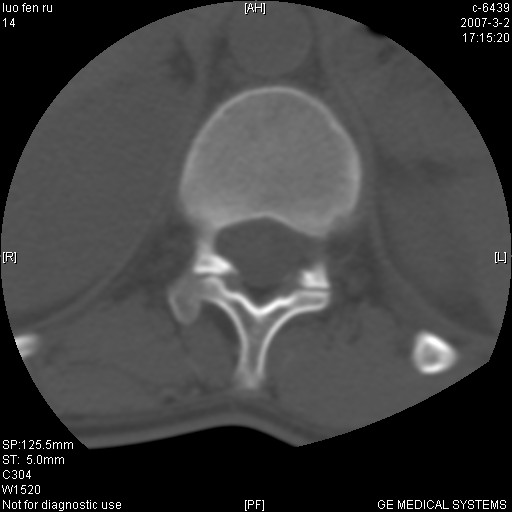

标题: CT6952:T11椎体病变请讨论

女,19岁.背部疼痛一月余.自诉幼时有个外伤史.

腰椎平片示,t11椎体呈楔形改变,椎间隙未见异常.

边缘硬化、增生复合陈旧性骨折。

结核:好发于胸椎,其次为腰椎,相邻椎体受侵,椎间隙变窄,椎体变扁,椎旁或腰大肌冷脓肿形成。

许莫氏结节形成

t11椎体前缘不规则形骨质破坏,周围有硬化边,软组织肿块不明显,首先考虑:骨嗜酸性肉芽肿 。期待随访结果。